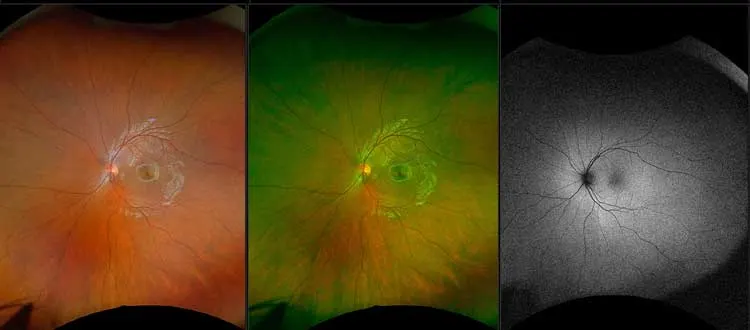

Stargardt’s or macular dystrophy refers to a set of hereditary progressive degenerative eye diseases that primarily affect the macula of the retina thereby causing gradual loss of central vision. For the people diagnosed, the task of moving from the point of diagnosis to that of proper management is often quite a challenging process riddled with